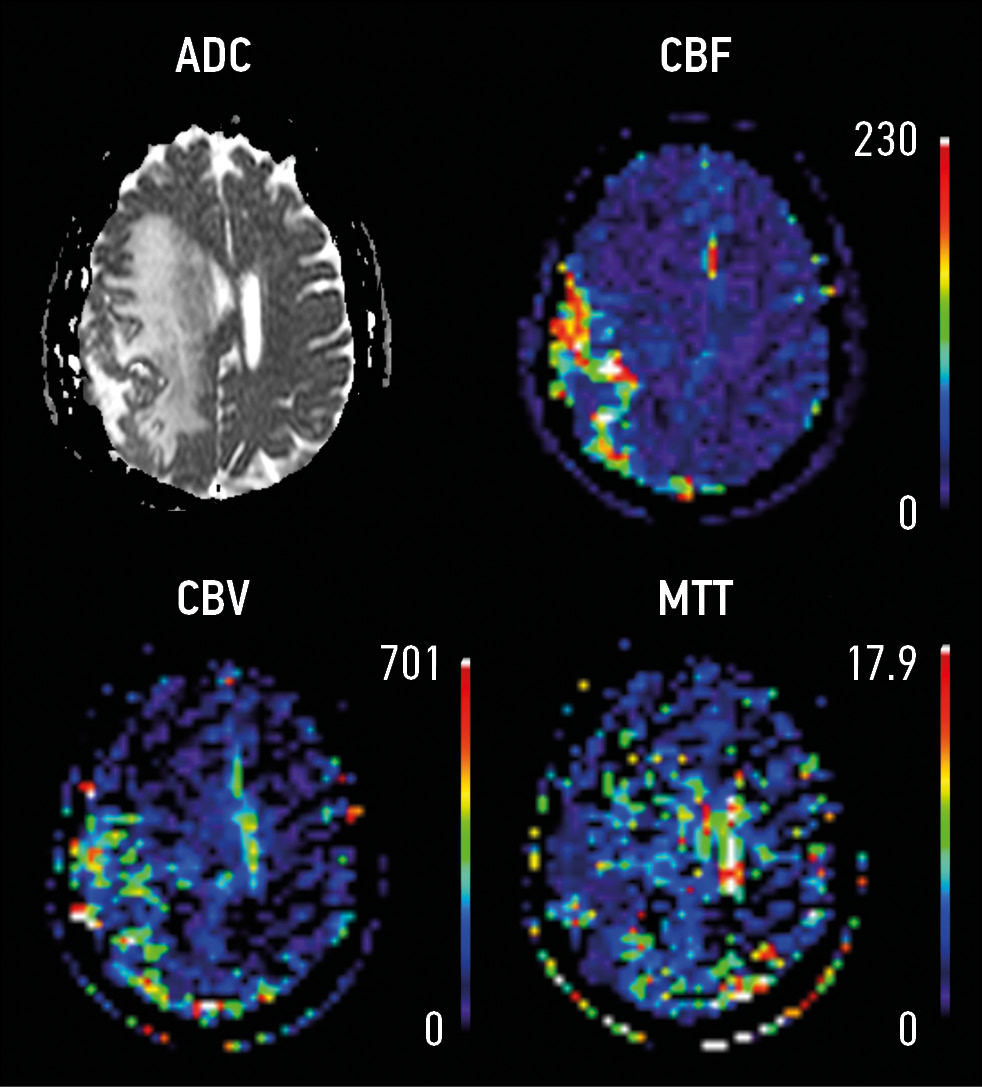

In group 1, a multivariate linear regression analysis revealed that in patients with verified meningioma (n = 66), the maximum size of the main lesion zone increased the coefficient of volumetric regional cerebral blood flow (rCBF) from the zone of perifocal changes by 3.3 times (βcoef. 3.3; confidence interval 1.27–5.28), p = 0.003 (Fig. 1); however, it reduced the cerebral blood volume (rCBV) by four times (βcoef. 4; CI −7.46 to −0.71), p = 0.02 (Fig. 2).

Fig. 1. Linear regression analysis: relation between tumor size and CBF rate

The analysis of DCE values in group 2 did not reveal a correlation between the tumor size and DCE from the area of perifocal changes, in contrast to perfusion maps (Fig. 3).

Fig. 3. Atypical meningioma: ADC ― apparent diffusion coefficient; CBF ― cerebral blood flow, CBV ― cerebral blood volume, MTT ― mean transit time. Perfusion techniques are not required